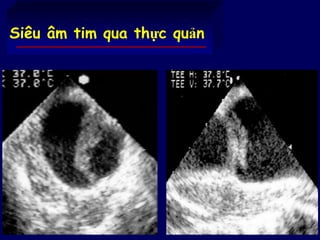

Siêu âm tim qua thực quản

74 Siêu âm timqua thực quản

• Siêu âm qua thực quản cho thấy các bóng khí ở nhĩ

trái và thất trái khi hít vào và biến mất khi ngừng thở

• Giảm áp lực đường thở (Pep, Vt) có thể giảm tắc

mạch do hơi »

Saada M, Am J Respir Crit Care Med,1995